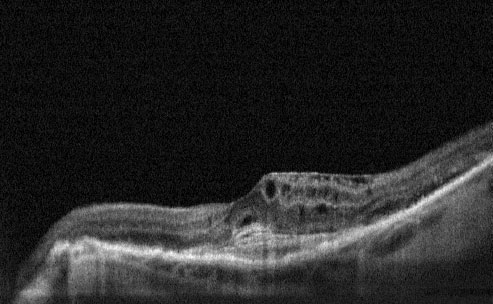

Pre-Treatment- Cystoid Macular Oedema and CNV